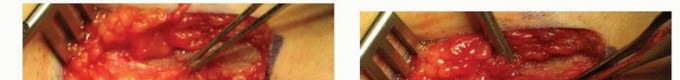

OUTCOMES

In reports of poor results from septic arthritis, 75% involve the hip joint.

Severe sequelae with a destroyed femoral head are most commonly seen in newborns and infants and are often related to a delay in diagnosis and treatment (

FIG 5

).

Infants in particular should be followed for several years to document adequate development of the hip joint.

FIG 5 • This 3-year-old child had septic hip arthritis missed as an infant with a week-long delay in treatment, resulting in osteonecrosis of the right femoral head.